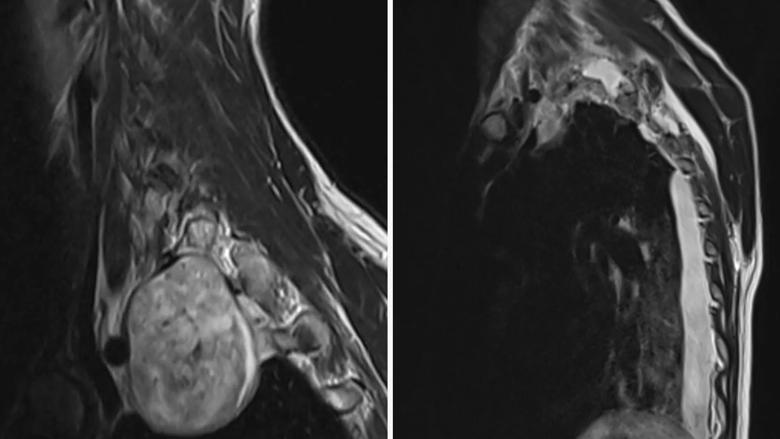

7 cm schwannoma at the intersection of the spine, lung and major arteries

Imaging depicting the 7 cm schwannoma in the superior mediastinum